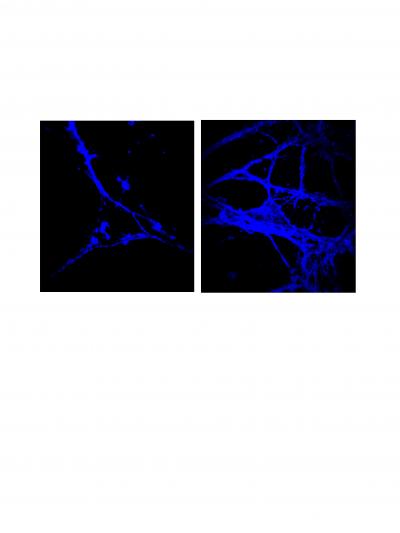

The Mayo researchers observed the abnormal accumulation of cholesterol in cultured neuronal cells in the laboratory and in the brains of animal models. They found that this happens only when the mutant Huntington's protein is expressed together with the molecule, caveolin-1. Caveolin-1 is the major structural protein of small vesicles called caveolae, which capture cholesterol and move it in and out of the neuronal membranes. When the researchers "knocked out" expression of caveolin, the neurons expressing mutant Huntington's protein stopped accumulating cholesterol.